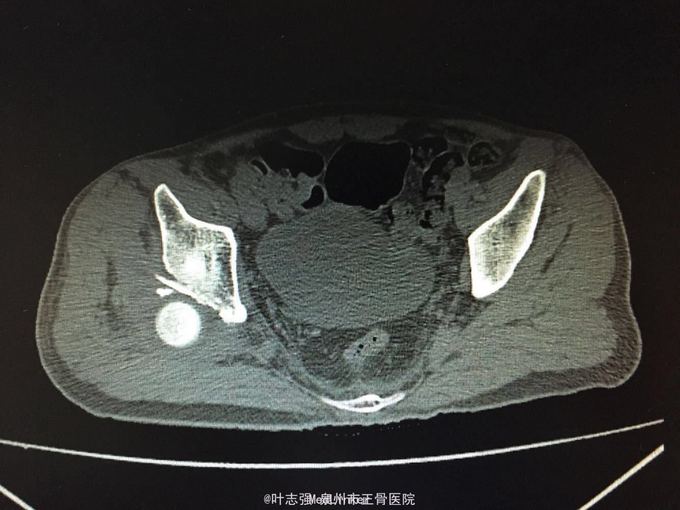

髋臼骨折伴髋关节后脱位ORIF

车祸致左髋部疼痛、活动受限1天。 53岁男性

左髋臼骨折伴髋关节后脱位 行生命支持,股骨髁上骨牵引,